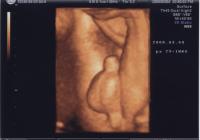

[30주] 엄마 뱃속의 KKOBI

세상 참 많이 좋아졌지. 뱃속에 있는 KKOBI의 모습을 볼 수 있으니 말이야~ KKOBI의 태동은 지금껏 시우가 초롱이로 있을 때 보다 훨씬 더 많이 움직이고 그 모습을 조금 떨어진 곳에서도 엄마 배의 움직임을 볼 수 있단다. KKOBI가 뱃속에 있으면서 많은 험난... -